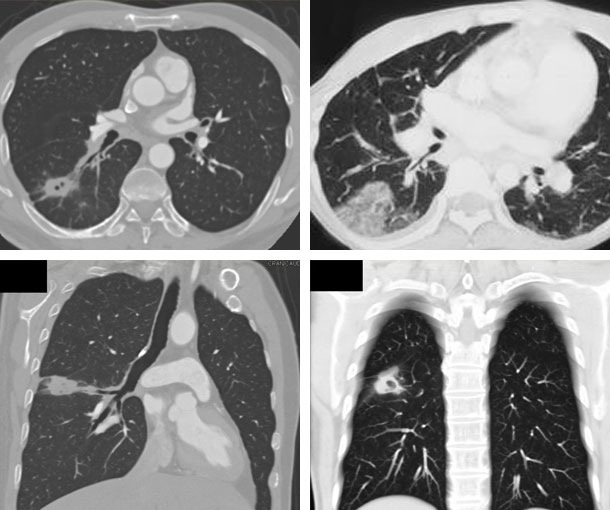

Chest CT Appearances

Adenocarcinoma In Situ (AIS) CT Findings

- Ground glass nodule

- Single mass

- Diffuse consolidation

- Multinodular forms